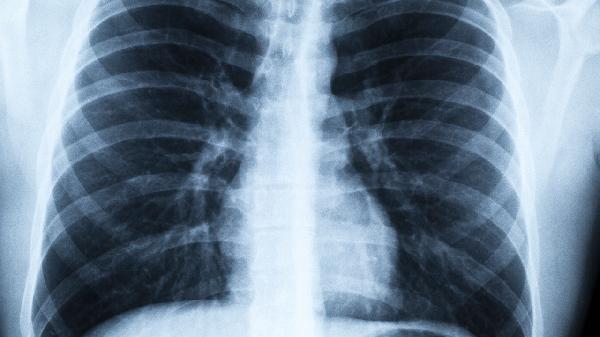

冬季警惕!这几种表现持续出现,当心肺癌找上门

最.近门诊遇到位50岁的张先生,连续咳嗽三个月不见好,起初以为是普通感冒,直到咳出血丝才慌忙就诊。CT结果显示的阴影让所有人心里一沉——这个沉默的杀手正在悄悄侵蚀他的肺部。

1.高危人群每年低剂量CT筛查

长期吸烟者、有家族史人群、接触石棉等致癌物的职业人群,建议将体检项目从胸片升级为CT,能发现毫米级的早期病变。